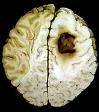

Điều trị u não và giảm triệu chứng bệnh sa sút trí tuệ:

Mặc dù artemisinin không thể hòa tan trong nước được, song nó có thể đi xuyên qua hàng rào mạch máu não (blood brain barrier) với nồng độ cao. Do đó, người ta có thể áp dụng lợi điểm này để điều trị tiêu diệt hoặc làm chậm lại phát triển của các tế bào khối u ở não và một số bệnh lý về não màng não khác. Bên cạnh đó, trong một thử nghiệm gần đây, alkaloid củaartemisia asiatica được chuyển hóa thành các phân tử nhỏ trong đường tiêu hóa và đi qua hệ thống mạch máu não. Những kết quả đó chỉ ra rằng thuốc có thể tác động như một chất ức chế acetylcholinesterase với một block beta độc tính trên thần kinh ở người gây ra tình trạng sa sút trí tuệ người lớn tuổi (Heo et al, Inhibitory effects of Artemesia alkaloids on acetylcholine sterase activity from PC12 cells, molecule cells, Jun 30:10(3):253-262)